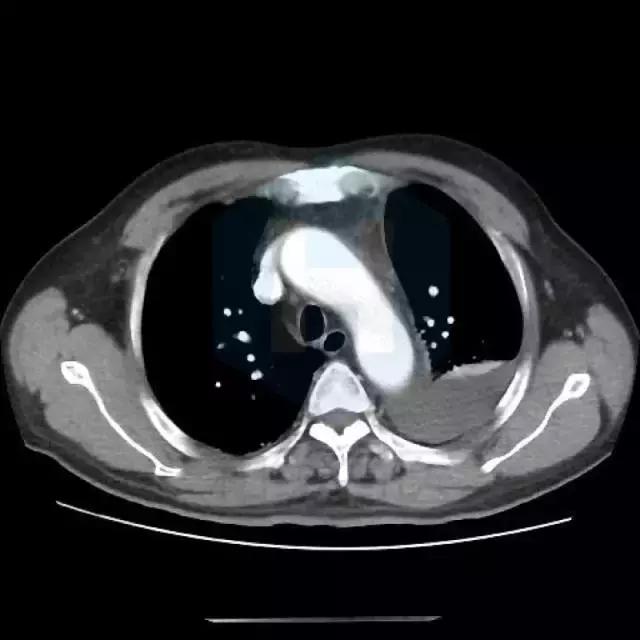

从CT来看,是比较典型的肺栓塞的表现,应该做肺动脉造影检查。

患者有胸痛,胸闷,1型呼吸衰竭,胸部影像示左下肺为“三角形”肺实变影伴胸腔积液,高度怀疑存在肺栓塞,建议行CTPA检查和肺核素通气/灌注现象检查。同时需排除肺栓塞原因,如肿瘤,自身免疫性疾病等。肺栓塞也会有黄疸和溶血表现。 胸痛特点和表现不符合心绞痛,左侧胸腔积液与左侧肺部病变有关。 患者黄疸考虑为溶血性黄疸,应行查找溶血原因,此外,血红蛋白有降落,便潜血阳性,有同时伴有失血可能,建议查血网织红细胞计数评价贫血情况,应行胃肠镜检查以明确消化道出血原因。 目前低价血症原因考虑不除外副肿瘤综合症可能,关注纠正电解质紊乱。 可视医院条件,建议安排下一步检查:胸部增强CT及CTPA,或肺通气/灌注检查,下肢及深静脉超声,血肿瘤标志物,血网织红细胞计数,自身免疫抗体(ANA,ENA,ANCA)等,胃肠镜检查。 由于目前有消化道出血风险,暂不建议抗凝治疗。密切视察。